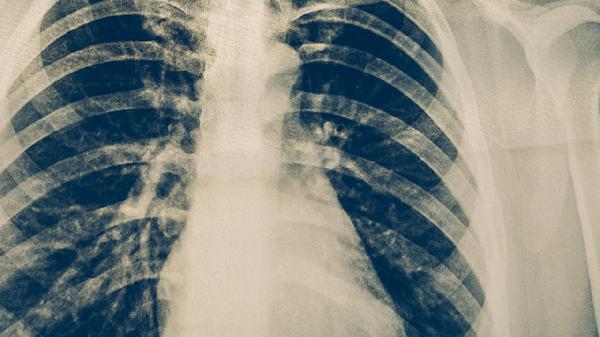

肺結(jié)核病的典型癥狀表現(xiàn)主要有咳嗽、咳痰、咯血、胸痛、發(fā)熱等。肺結(jié)核是由結(jié)核分枝桿菌感染引起的慢性傳染病,主要侵犯肺部,也可累及其他器官。

咳嗽是肺結(jié)核最常見的癥狀,早期多為干咳,隨著病情發(fā)展可出現(xiàn)咳痰??人猿掷m(xù)時間較長,通常超過2周,且普通止咳藥物效果不佳。肺結(jié)核患者的咳嗽多伴有午后低熱、夜間盜汗等全身癥狀。若出現(xiàn)長期不愈的咳嗽,應(yīng)及時就醫(yī)進(jìn)行結(jié)核菌素試驗或胸部X線檢查。